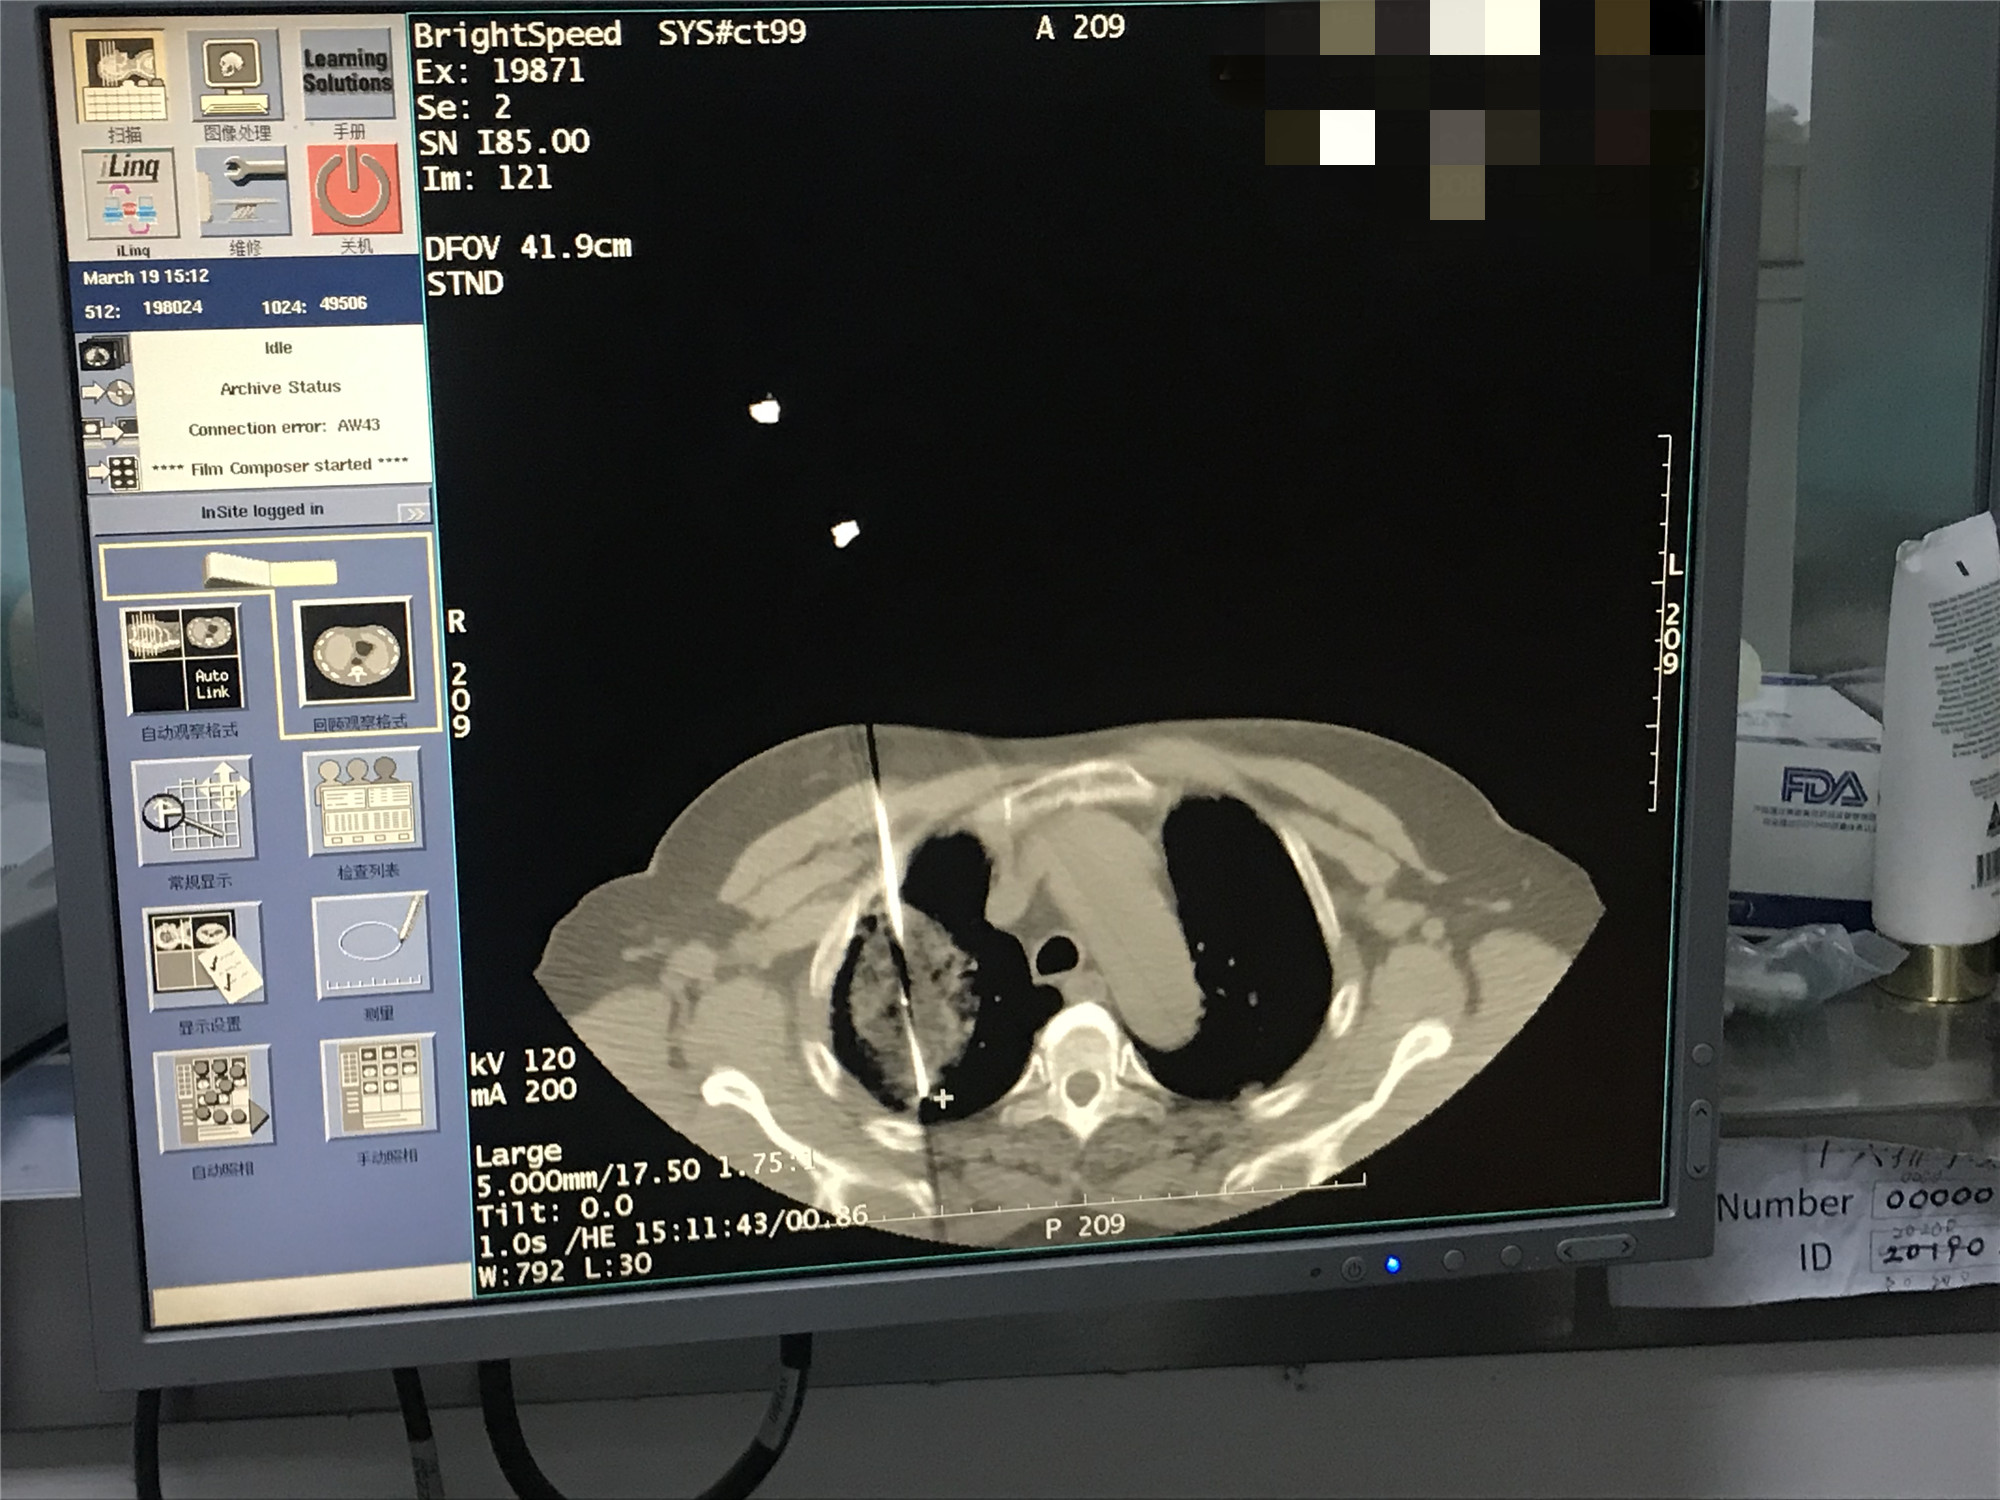

2021年3月份肺部氩氦刀手术

发布人:美国氩氦刀技术官方网站    发布时间:2021/9/22 15:44:51